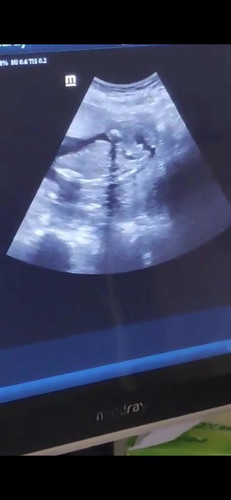

Boy or girl based on ultrasound

17wks6days pregnant, sabi ng ob sonologist parang boy dahil may lawit, based on your opinion mga mommies boy or girl po baby ko? ?

Yeah, I think a BOY. Pero, kung unsure ka momsh, pasecond opinion ka😊

Boy po dahil may balls 😁✌